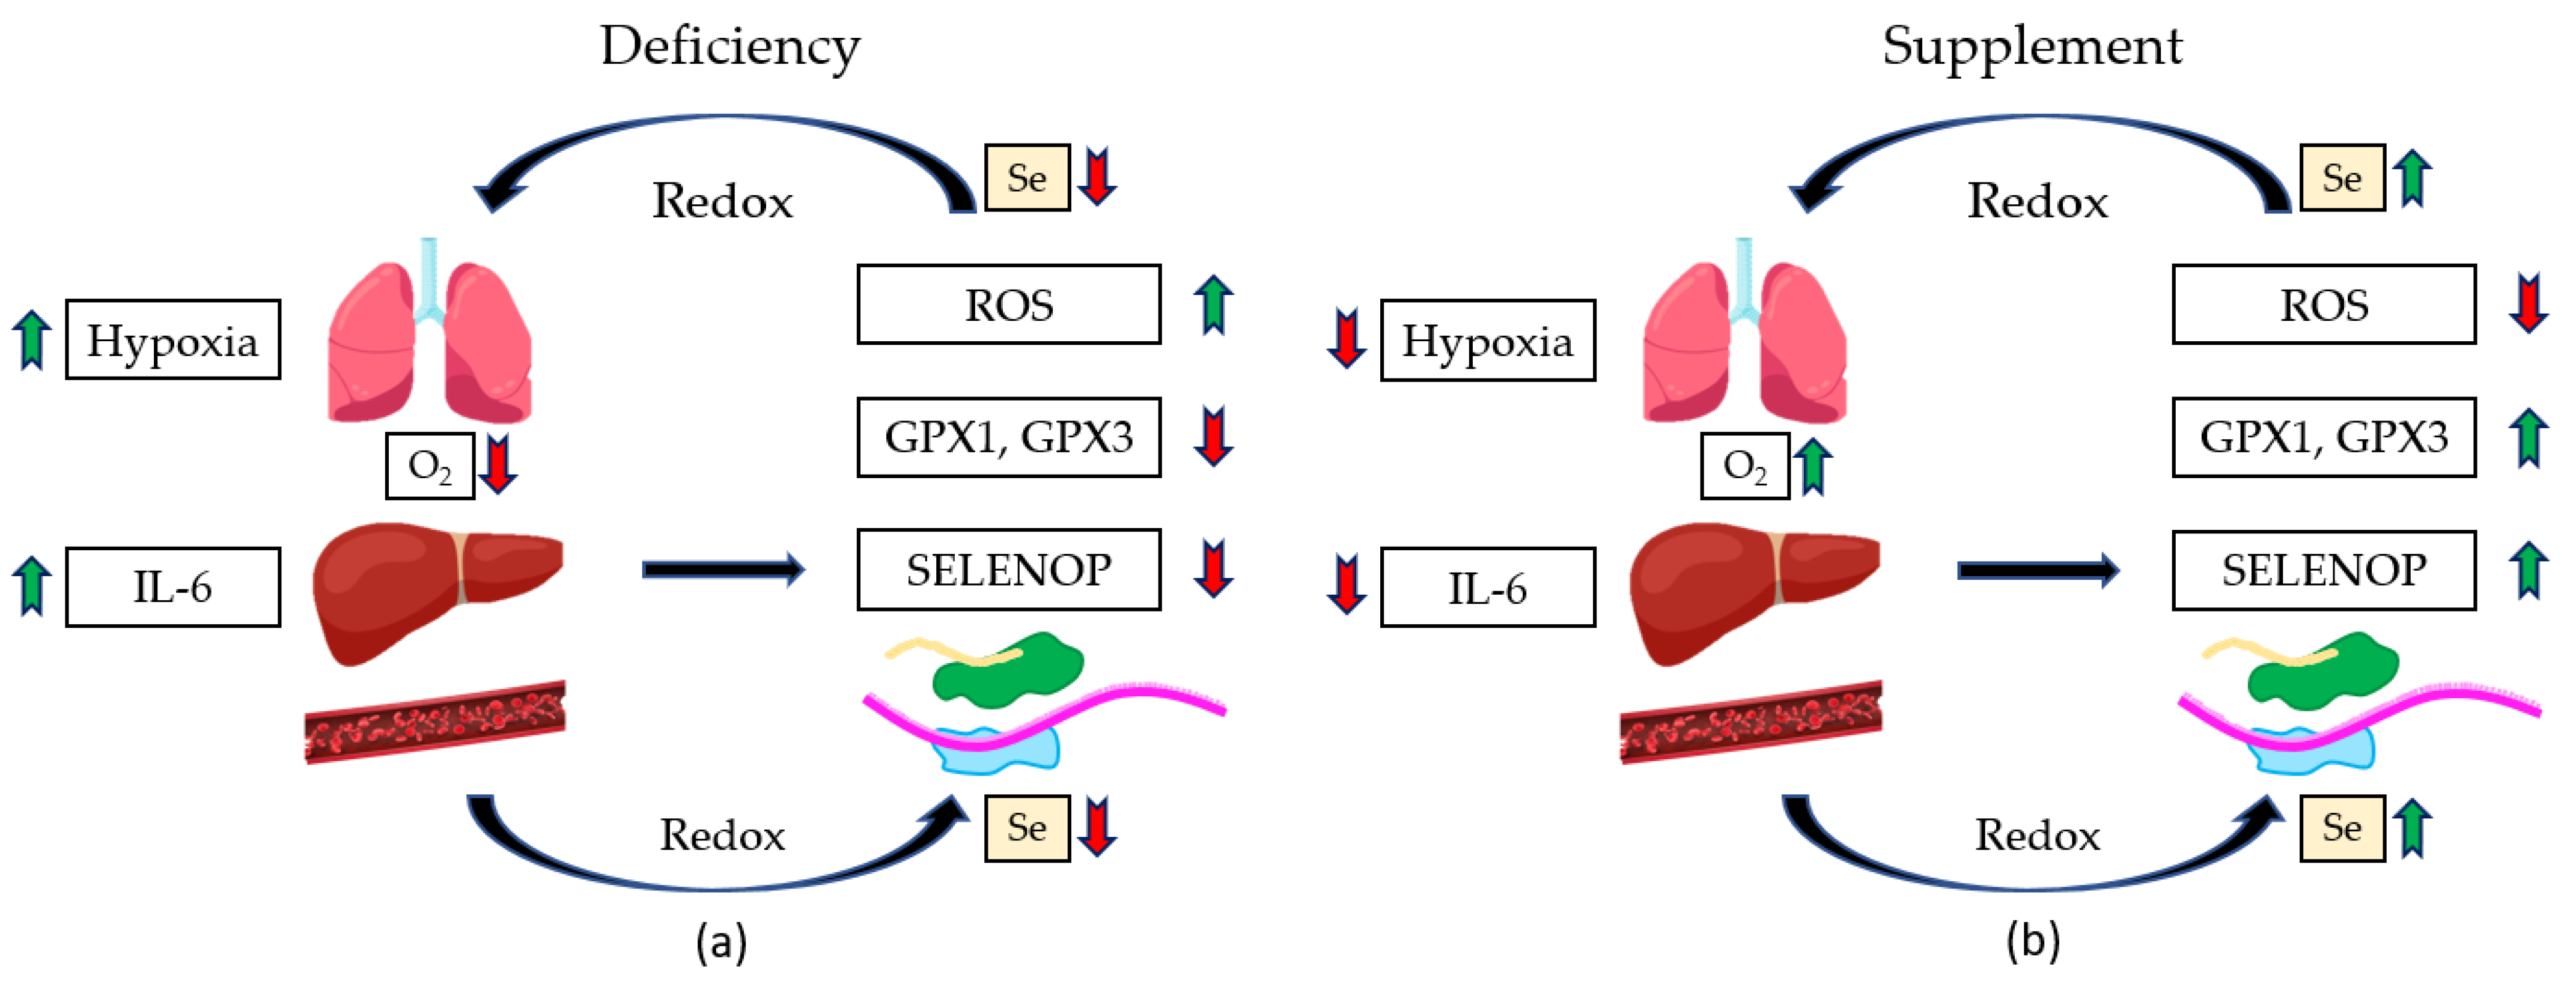

5. The Role of Selenium in Senescence and Ferroptosis

6. Benefits of COVID-19 Se Treatment and Related Sepsis Conditions